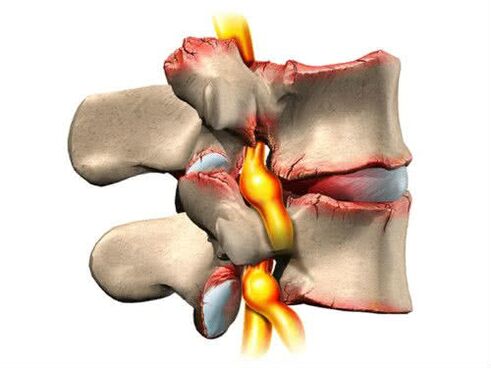

Osteochondrose ist ein degenerativer Prozess, der im Gelenkknorpel und im angrenzenden Knochengewebe auftritt. Ärzte definieren diese Krankheit als eine degenerativ-destruktive Schädigung der Wirbel und Bandscheiben: Sie verlieren Feuchtigkeit, nehmen an Höhe und Elastizität ab.

- Stadium der diskogenen Radikulitis. Der Faserring beginnt sich langsam zu verformen (Risse und Vorsprünge treten auf). Der Schmerz wird schärfer und plötzlicher, das Unbehagen macht sich deutlicher bemerkbar. Ein Symptom wie „Schmerzen im unteren Rücken“ tritt auf, die Gliedmaßen beginnen taub zu werden;

- Gefäß-radikuläres Stadium. Der fibrinöse Ring verliert vollständig seine Form. Von diesem Moment an können sich Hernien bilden. Röntgenaufnahmen sind sehr aufschlussreich. Die subjektiven Empfindungen der Patienten sind ausgeprägt (Schmerzen, starke Schmerzattacken, ständiges Unbehagen). Es treten häufig Muskelkrämpfe auf und die Leistungsfähigkeit nimmt dramatisch ab. Wenn die Nervenfasern leiden, sind erste Anzeichen einer Funktionsstörung der inneren Systeme vorprogrammiert;

- Wenn die Höhe der Wirbel abnimmt, beginnt die Reibung zwischen ihnen. Als Kompensationsmechanismus können Osteophyten auftreten. Dabei handelt es sich um spezielle Osteowachstumsformen, die dazu beitragen, den Bereich zu stärken, in dem die Reibung am stärksten war. Osteophyten können jedoch entzündliche Prozesse in den umliegenden Weichteilen verursachen und das pathologische Bild verschlechtern.